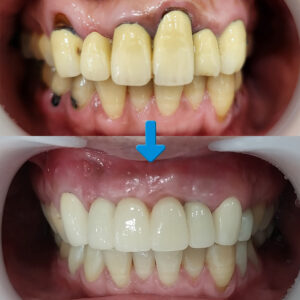

오늘은 임플란트 주위염으로 잇몸뼈의 소실이 있어 재 식립을 진행하신 분의 사례를 소개해 드리겠습니다.

환 자분께서는 오른쪽 위아래의 어금니가 잇몸이 많이 붓고 무언가 저작할 때마다 아픔과 함께 심어논 치아가 흔들린다는 주소로 내원해 주셨는데요. 파노라마 사진을 보시면 오른쪽 위아래의 어금니 치아에 염증성 소견이 발견되었습니다.

오른쪽 위 큰 어금니 2개의 경우 염증이 많이 있어, 고름이 차고 많이 흔들리는 모습을 보였습니다. 그동안 치과에 오셔야지 하면서도 버티셨다가 결국 주변 분들에게 가정동임플란트를 추천 받아 리더탑으로 오시게 된 것인데요.

환 자분의 경우에는 염증이 이미 오랜 기간 방치되어 서서히 잇몸뼈를 소실시켰고 주위염이 생기면서 기존에 심어진 임플란트를 제거하지 않으면 주변의 다른 부위에도 영향을 미칠 수 있어 재수술이 불가피한 상황이었습니다.

따라서 오른쪽 위의 염증이 이미 많이 진행된 큰 어금니 2개와 오른쪽 아래의 두 번째 큰 어금니 치아는 발치를 가장 먼저 진행하고, 내부의 염증을 제거한 후, 빈 공간에 임플란트 식립을 하기로 치료 계획을 세웠습니다. 우선 발치를 진행하였고, 발치 후의 상태를 보시면 남은 잇몸뼈가 거의 없는 것을 확인할 수 있습니다.

인공치근이 제대로 잇몸뼈에 유착될 수 있도록 충분한 기간을 가져 기다린 후, 추후에 치아머리 역할을 하는 보철물을 얹어 마무리하는 것으로 하는 것으로 상의하였습니다.